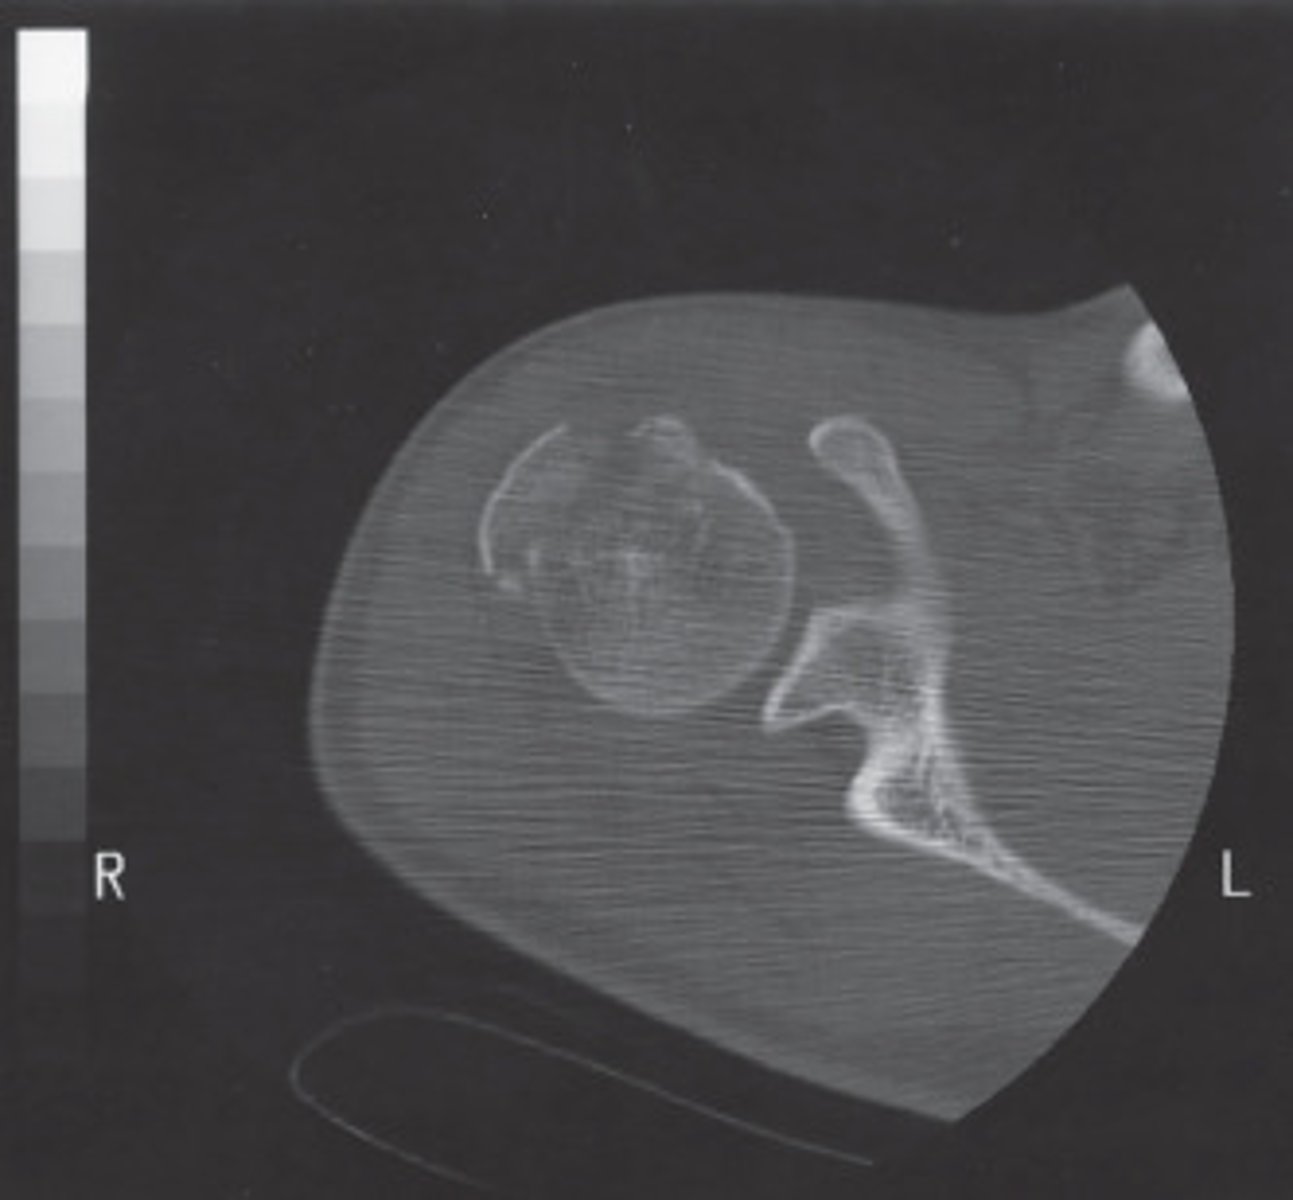

High Spatial Frequency

What type of algorithm would be best suited to demonstrate the bony details of this shoulder?

<p>What type of algorithm would be best suited to demonstrate the bony details of this shoulder?</p>